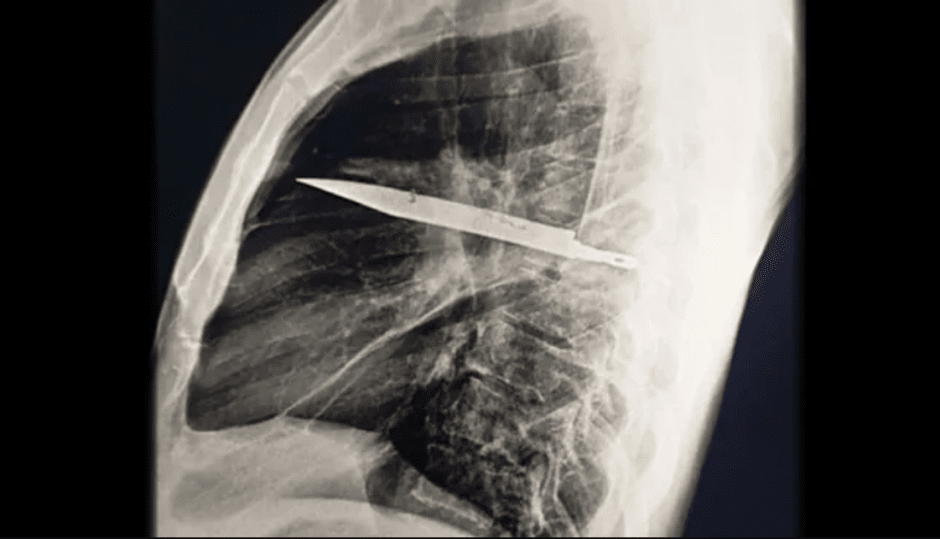

рентгеновский снимок ножа, застрявшего в груди мужчины

Рентген и КТ показали крупное металлическое лезвие, проходящее через грудную клетку от спины к передней части. Вокруг него образовалась капсула из соединительной ткани, что позволило пациенту жить без осложнений долгие годы.